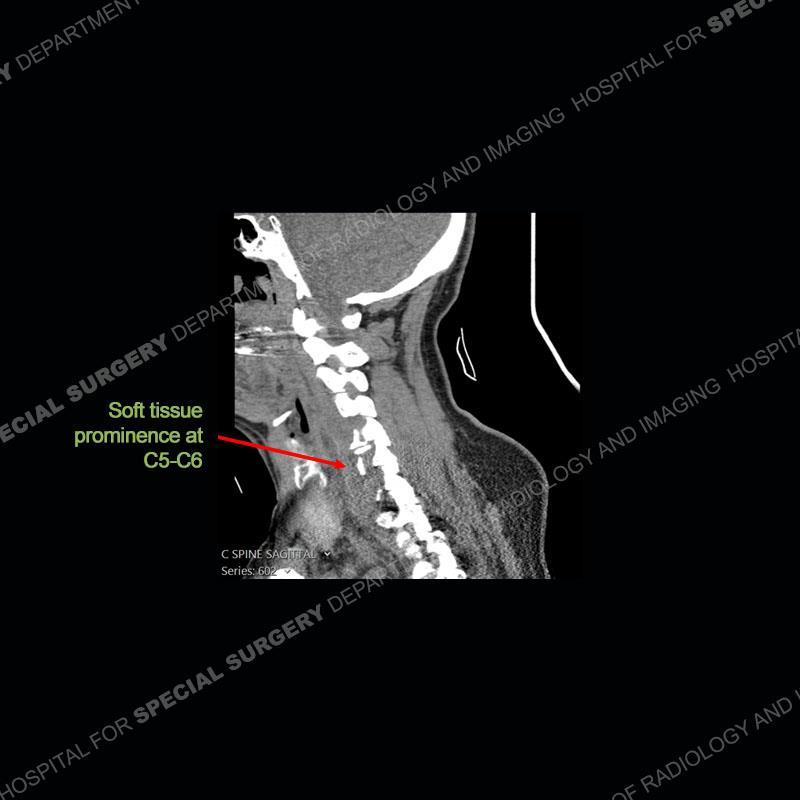

The radiographs demonstrate a prevertebral soft tissue fullness centered at C5-C6 that persists even on extension. There is a slight loss of disc height at C5-C6. The CT more readily shows the prevertebral soft tissue swelling at C5C6 where there is a punctate focus of gas. On the MRI, there is a marked amount of edema and a heterogeneous collection in the prevertebral soft tissue at C5-C6. Edema is present of the C5 and C6 vertebral bodies with a loss of the normal architecture about the disc space. A heterogeneous epidural collection has formed that causes compression of the spinal cord asymmetric to the left side and also precipitates severe left sided neural foraminal stenosis.